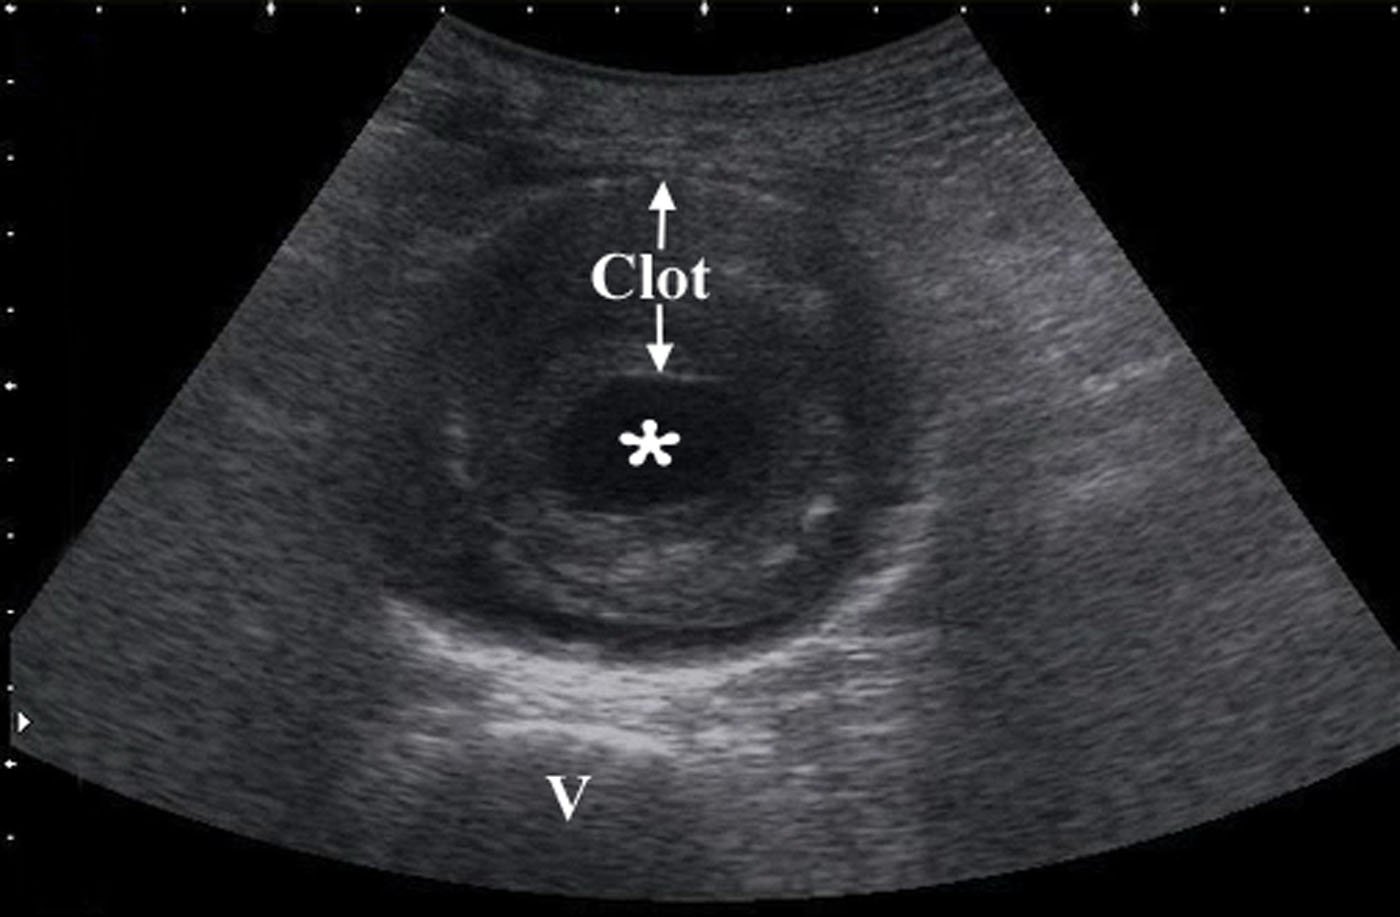

- Aorta and iliac arteries are measured from outer wall to outer wall. Normal abdominal aorta diameter is less than 3 cm. AAA is defined as greater than 3 cm.

- Obtain measurements of aorta from outer wall to outer wall. Since aneurysms will often contain a thrombus, and with time this becomes calcified and hyperechoic, one may accidentally mistake the inner rim of the thrombus for the aortic wall. Doing this will lead a falsely decreased measurement of the true aortic diameter, possible causing the aneurysm to be missed completely.

- Figure 9. Transverse view of a 7 cm AAA with intraluminal clot (* on the lumen, “v” denotes vertebral body)